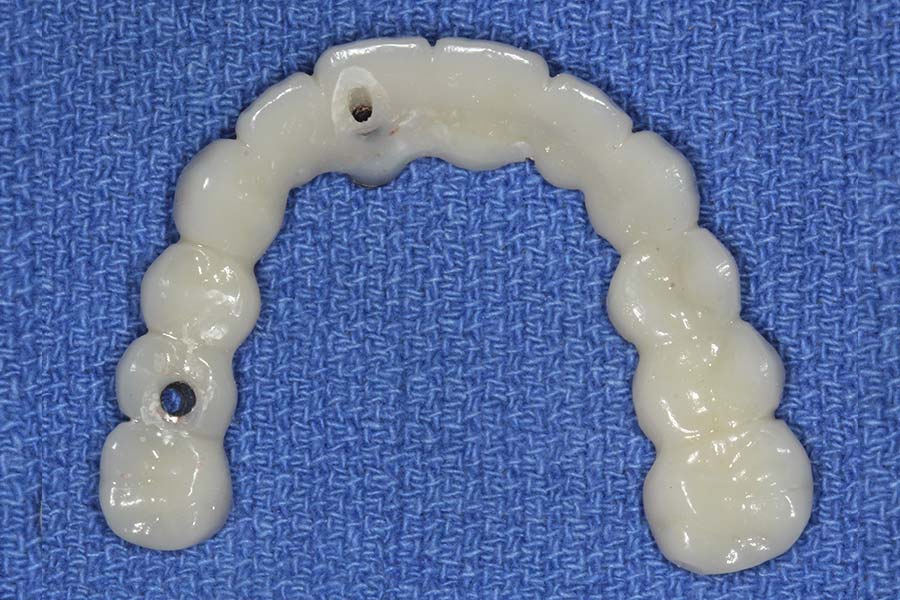

Smile GalleryImplant RestorationsFull Mouth Implant Restoration Full arch zirconia implant bridge (full smile) 1 of 37 Pre-op full smile Pre-op lips retracted Pre-op panoramic x-ray Extraction of strategic teeth Placement of implants Extraction of some remaining teeth after verification of adequate implant stability Occlusal view Post-op panoramic x-ray Immediately fabricated provisional restoration (tissue side view) Immediately fabricated provisional restoration (occlusal side view) Immediate provisional delivered on day of surgery Immediate provisional 2 weeks later Scalloped tissue developed from the provisional at 2 weeks Jig used for making a master impression Provisional in place (full smile) Provisional in place (lips retracted) Provisional in place (right side) Provisional in place (left side) Wax try-in (full smile) Wax try-in (right side full smile) Wax try-in (left side full smile) Wax try-in (full face, lips together) Wax try-in (full smile) Wax try-in (right side) Wax try-in (left side) Wax try-in (lips retracted) Full arch zirconia implant bridge on master cast (frontal view) Full arch zirconia implant bridge on master cast (occlusal view) Implant positions and soft tissue representation on master cast (occlusal view) Soft tissue representation on master cast (frontal view) Full arch zirconia implant bridge (tissue side view) Soft tissues on day of delivery (occlusal view) Soft tissues on day of delivery (frontal view) Full arch zirconia implant bridge delivered (lips retracted) Full arch zirconia implant bridge (lips retracted, close up) Post treatment panoramic x-ray Full arch zirconia implant bridge (full smile)